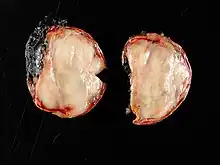

Pathologically, ganglioneuromas are composed of ganglion cells, Schwann cells and fibrous tissue.[5] Ganglioneuromas are solid, firm tumours that typically are white when seen with the naked eye.